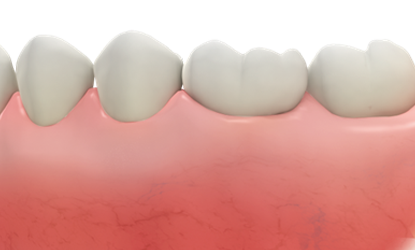

What if leave as is after tooth extraction?

- Deformation of gap between teeth

- Impact on alignment & health of remaining teeth

- Absorption of gingival bone over time (making it difficult to wear dentures)

- Decreased confidence due to esthetic impact

- Degradation of digestive function due to inability to chew properly

Gap deformation between teeth

Gap deformation between teeth

Impact on alignment & health of remaining teeth

Impact on alignment & health of remaining teeth

Absorption of gingival bone over time

Absorption of gingival bone over time